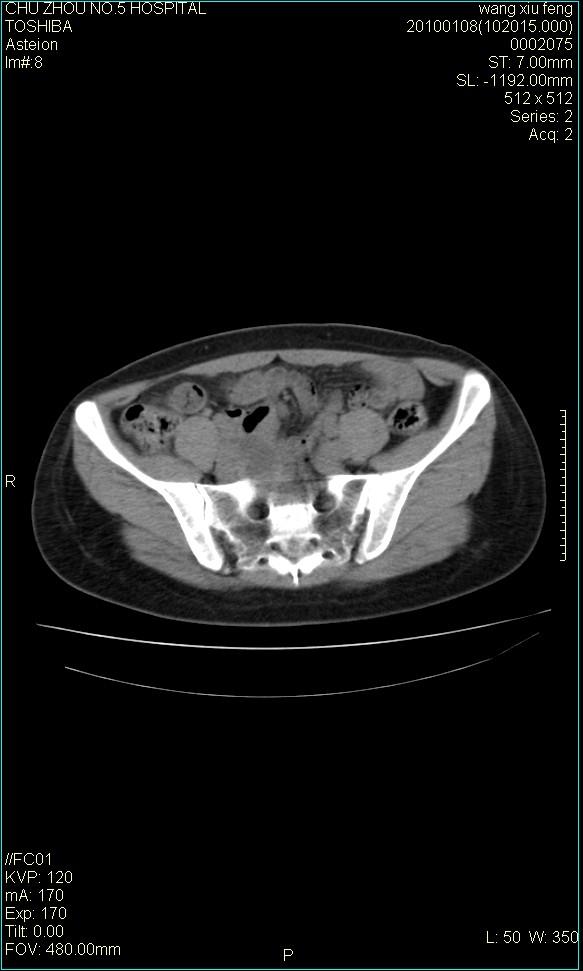

f-41,左乳腺ca术后4年,b超示:子宫右上方囊性包块约5.5*3.4cm,前日行胸部ct平扫未见明显异常。

考虑右侧卵巢囊腺瘤?

右侧卵巢囊肿或小囊腺瘤。

考虑右侧卵巢囊腺瘤?建议增强!

考虑右侧卵巢囊腺瘤。

考虑右侧卵巢囊性占位性病变(囊肿?囊腺瘤?)。